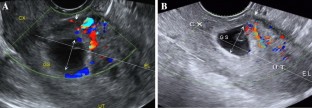

Fig. 1

Fig. 2